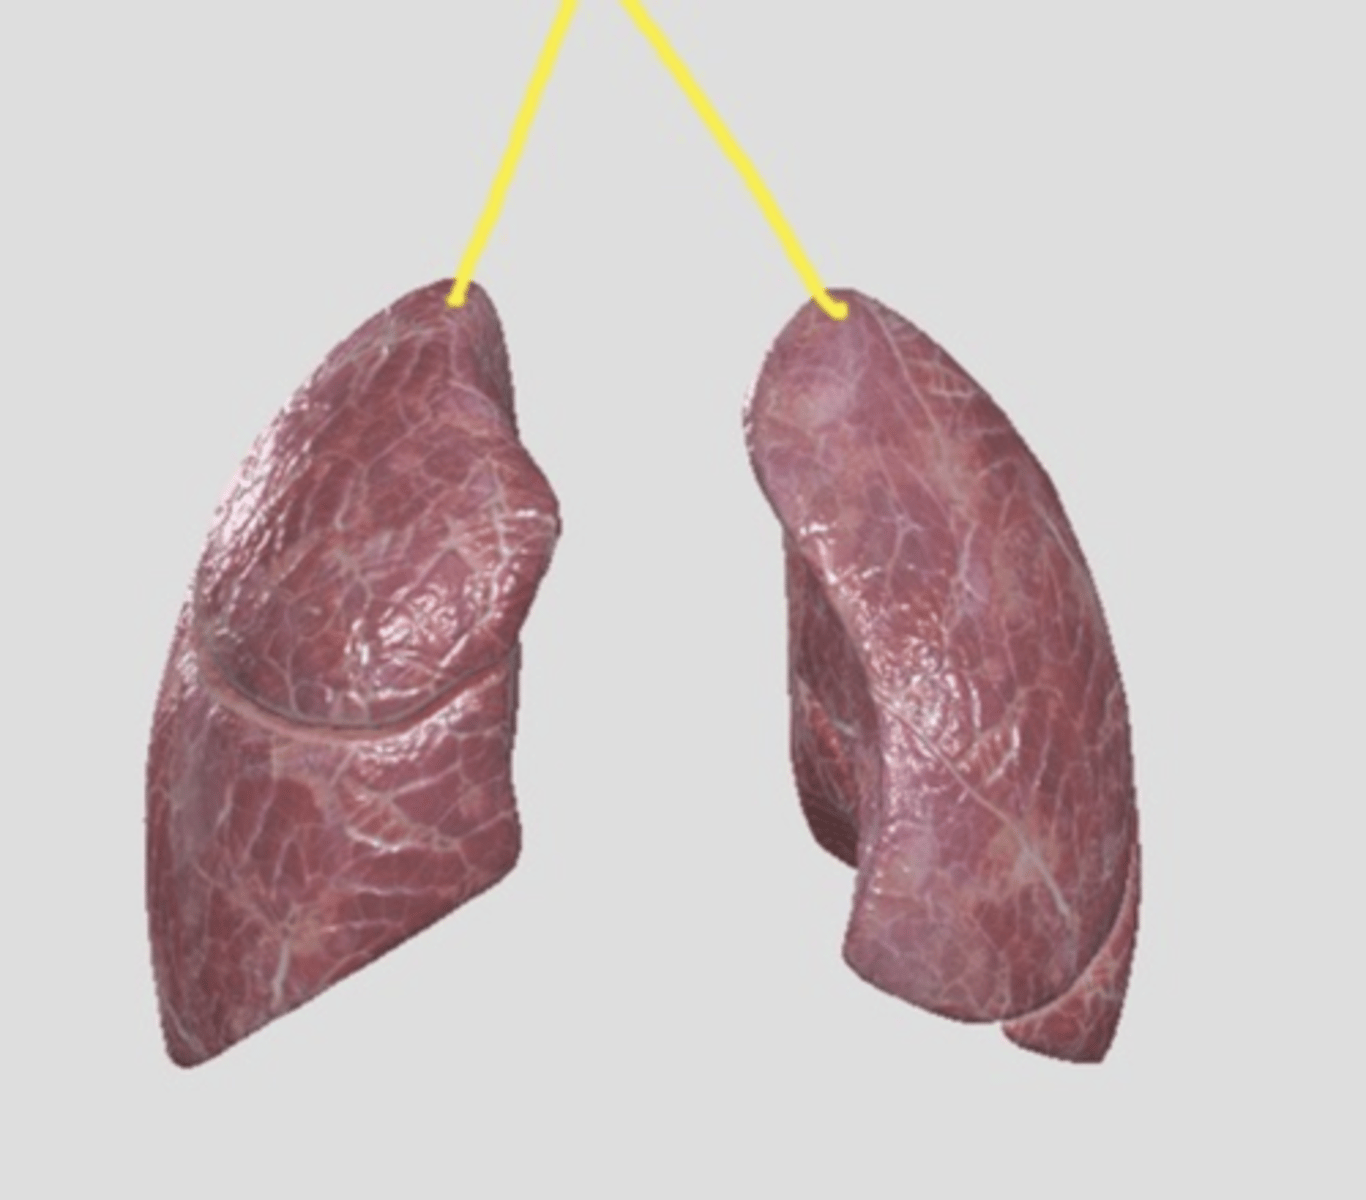

lung (normal)

smoker's lung